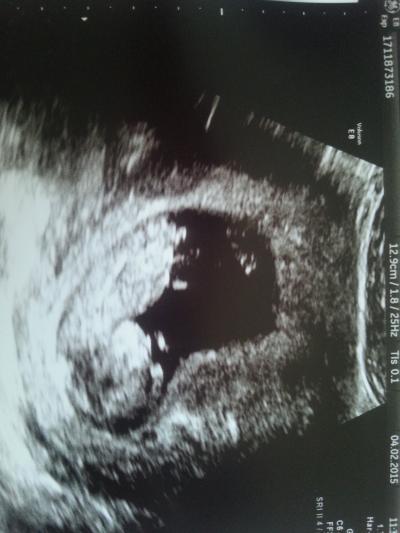

So nun können wir mit stolz unseren kleinen troll vorweisen. 5, 7 cm groß und anscheind nen ruhiger. Nfm ist super. Herzlein hat geschlagen, mussten ihn mehr mals schubsen damit es wach wird und wir die messung mache konnten. Als es dan wach war drete es uns doch tatsächlich den hintern zu. Fantastisches erlebnis, mein man ist nun hin und weck. Und was man nicht alles sehen kann. Wurde ne woche zurück gesetzt so bin ich eigentlich 11+6 Und Et hat sich nur um einen tag verschoben auf den 19 August.

Bild zu Es ist Liebe - Forum für August - Mamis